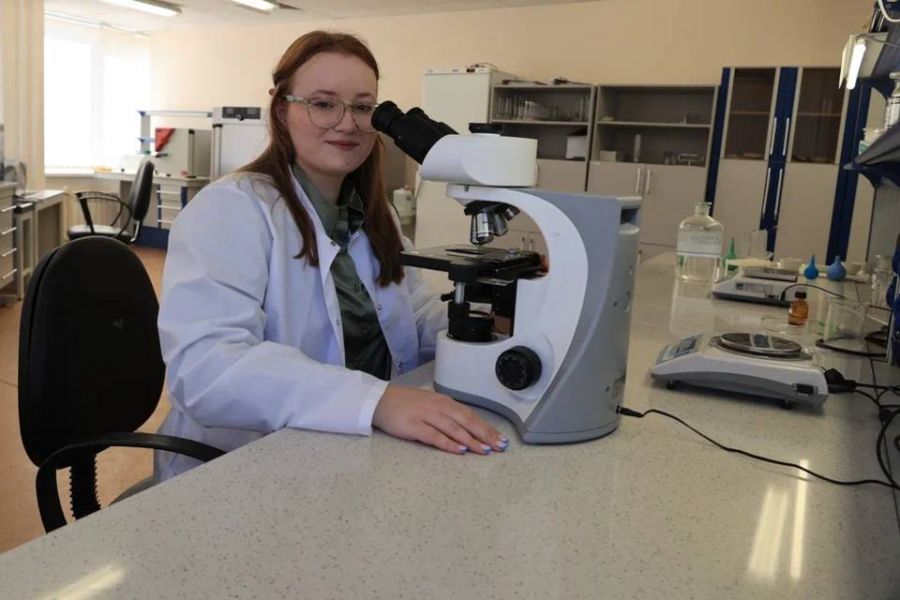

Ученые ВолгГМУ исследуют особенности хронических заболеваний у жителей Волгоградской области

На кафедре биологии ВолгГМУ Минздрава России началась реализация гранта для комитета здравоохранения Волгоградской области по теме «Региональные клинико-морфологические особенности хронических воспалительных заболеваний желудочно-кишечного тракта как предикторов заболеваний с потенциально высоким риском опухолевой трансформации».

Одолеть боль: студентка из Волгограда разрабатывает препарат против рака

Одолеть боль: студентка из Волгограда разрабатывает препарат против рака

Студентка 4 курса Волгоградского государственного медицинского университета Анастасия Дробышева исследует свойства портулака огородного. Будущий провизор уверена, что препарат, полученный из этого чудодейственного растения принесет большую пользу онкобольным.